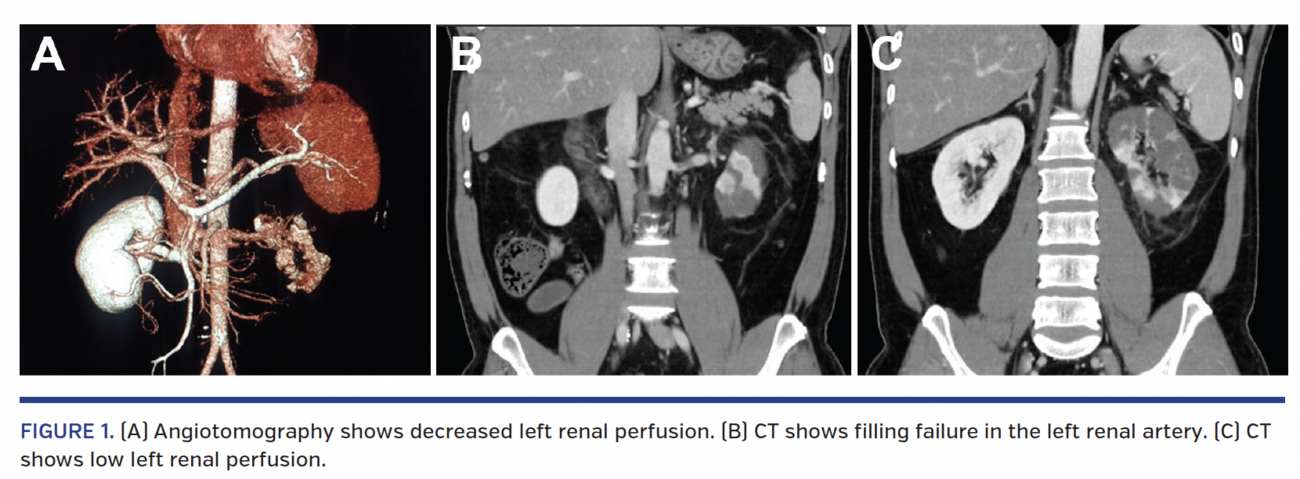

Before persistent pain, we chose to do a renal arteriography to evaluate percutaneous approach; it highlighted a high thrombotic load in the left renal artery (Figure 2; Videos 1 and 2) with a decrease in the nephrographic effect. In view of the patient’s clinical picture and angiographic findings, we chose local intra-arterial thrombolysis.

We performed selective catheterization of the left renal artery, followed by bolus infusion of alteplase 15 mg by microcatheter (Video 3). More diluted injections were then given over a period of 30 minutes for a total of 50 mg. Immediate arteriography showed a maintained pattern, but the patient experienced a slight improvement in the pain. After 6 hours of the procedure, the patient was asymptomatic.

New renal arteriography was performed after 5 days, and showed no evidence of thrombus, with improvement of the nephrographic effect (Videos 4-6). At hospital, he was kept under full anticoagulation with enoxaparin. He was discharged in good clinical condition with normal renal function. Rivaroxaban, bisoprolol, enalapril, and rosuvastatin were prescribed.